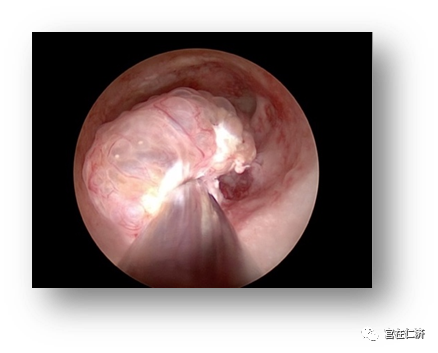

4. Q: 内膜息肉怎么明确诊断?

A:诊断性宫腔镜是最准确的诊断方法,并可以同时评估病变的大小和特性。此外常用的诊断方法还有经阴道超声检查,子宫输卵管碘油造影,盆腔核磁共振等。我们中心采用2.9mm口径的Trophy诊断镜,无需麻醉,没有性生活的病人也可以进行诊断操作。

5. Q:子宫内膜息肉怎么治疗?

A: 药物治疗对子宫内膜息肉的作用有限。手术治疗是内膜息肉最常用的治疗手段,目前指南推荐宫腔镜手术取代盲目刮宫作为内膜息肉的首选治疗。我们中心采用的IBS刨削装置,手术时间短,息肉切除完整,且没有电损伤,可以较好的保护内膜功能